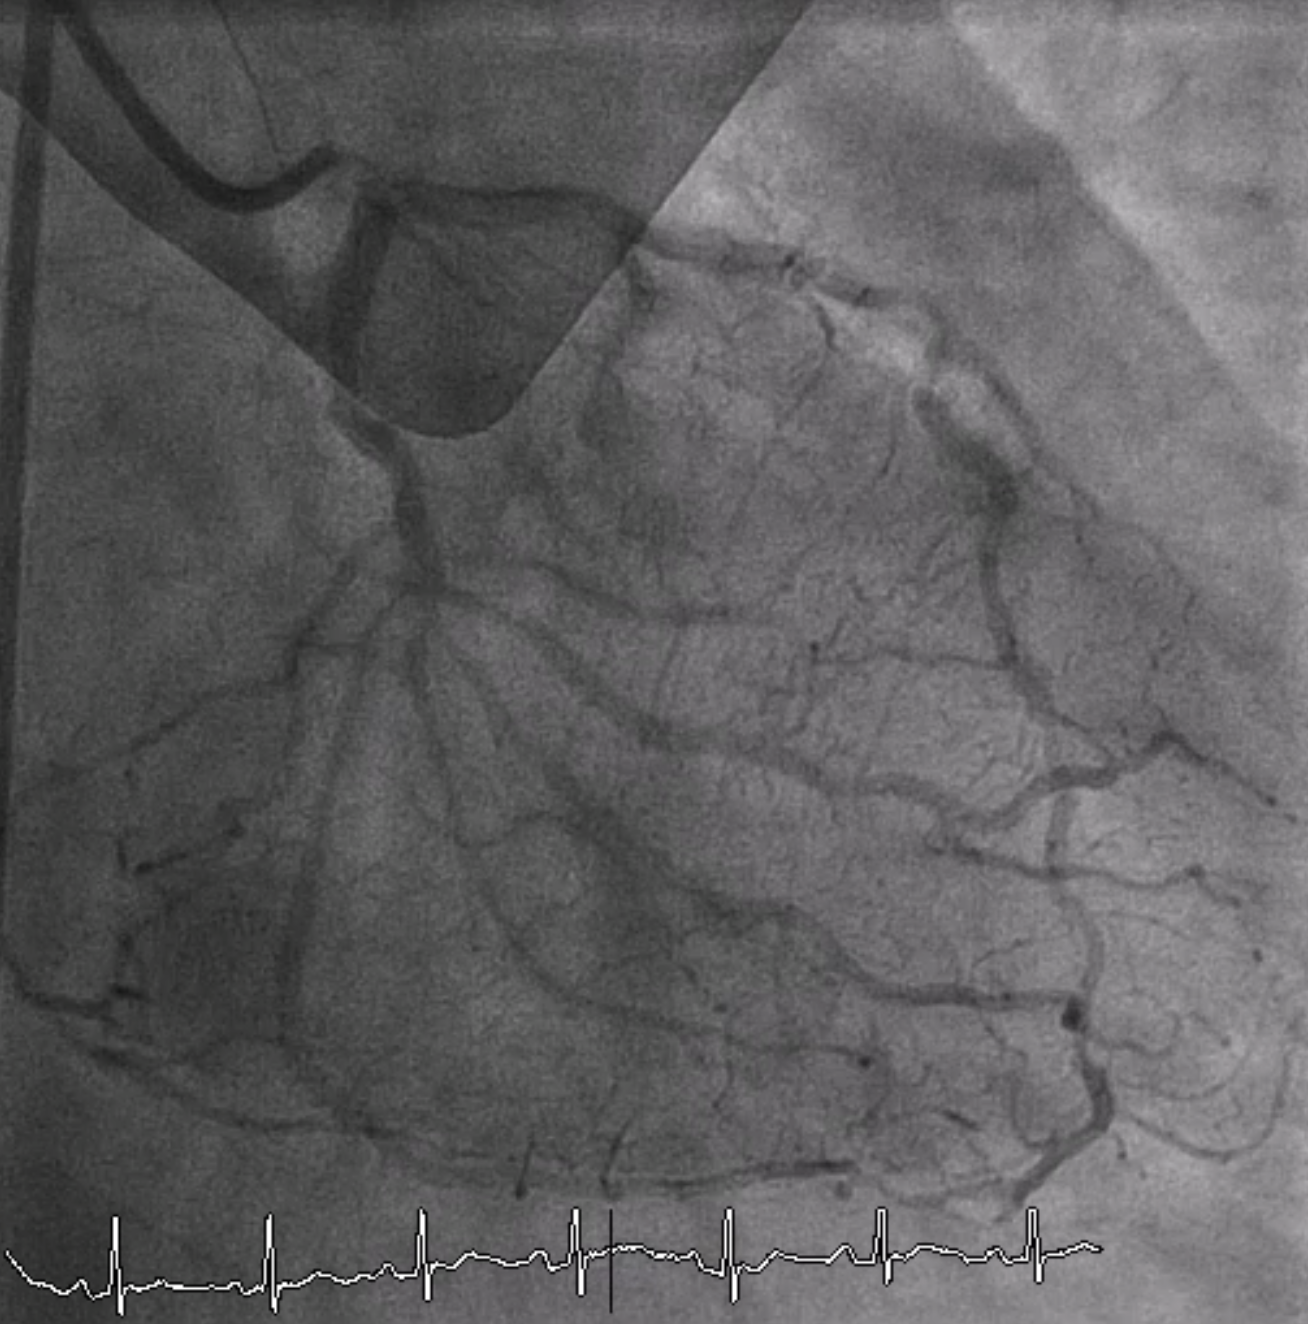

Relevant Catheterization Findings

Coronary angiography revealed total occlusion at proximal RCA with collateral circulation from conus branch, LAD and LCx to RCA. 70-80% stenosis at proximal to mid LAD and 50% stenosis at distal Lcx and OM.